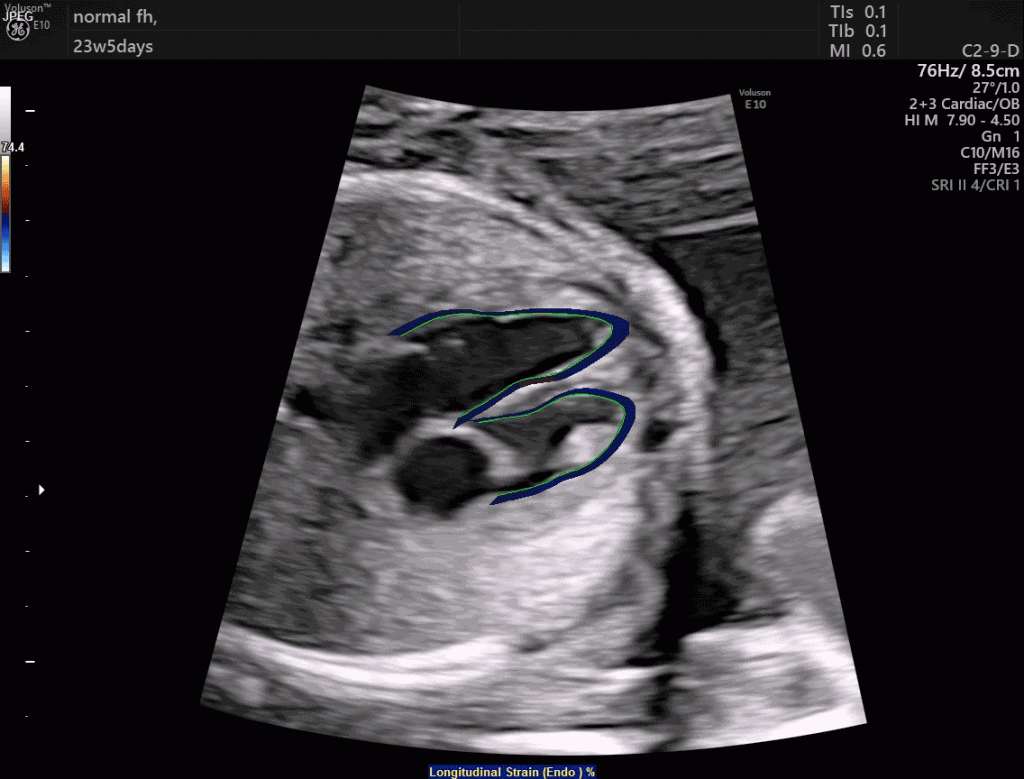

width= GE Healthcare's fetalHQ software is making it easier for doctors to spot congenital heart defects. Image credit: GE Healthcare.

As a company with a significant presence in medical technology and life sciences, GE Healthcare creates many products that improve the lives of mothers and their babies. Among the more difficult-to-spot problems with babies are congenital heart defects. GE Healthcare recently developed software called fetalHQ that runs on the Voluson ultrasound system used to image pregnant women. The software allows clinicians to simultaneously examine the size, shape and the contractility of the fetal heart in just three minutes. The idea behind fetalHQ came from maternal fetal medicine specialist Dr. Greggory DeVore, who modified existing methods of examining heart ventricles in older patients to apply to those in utero. Congenital heart defects affect one out of every 110 babies born around the world — with nine out every 10 occurring with mothers who had no risk known risk factors or anything concerning about their pregnancy.